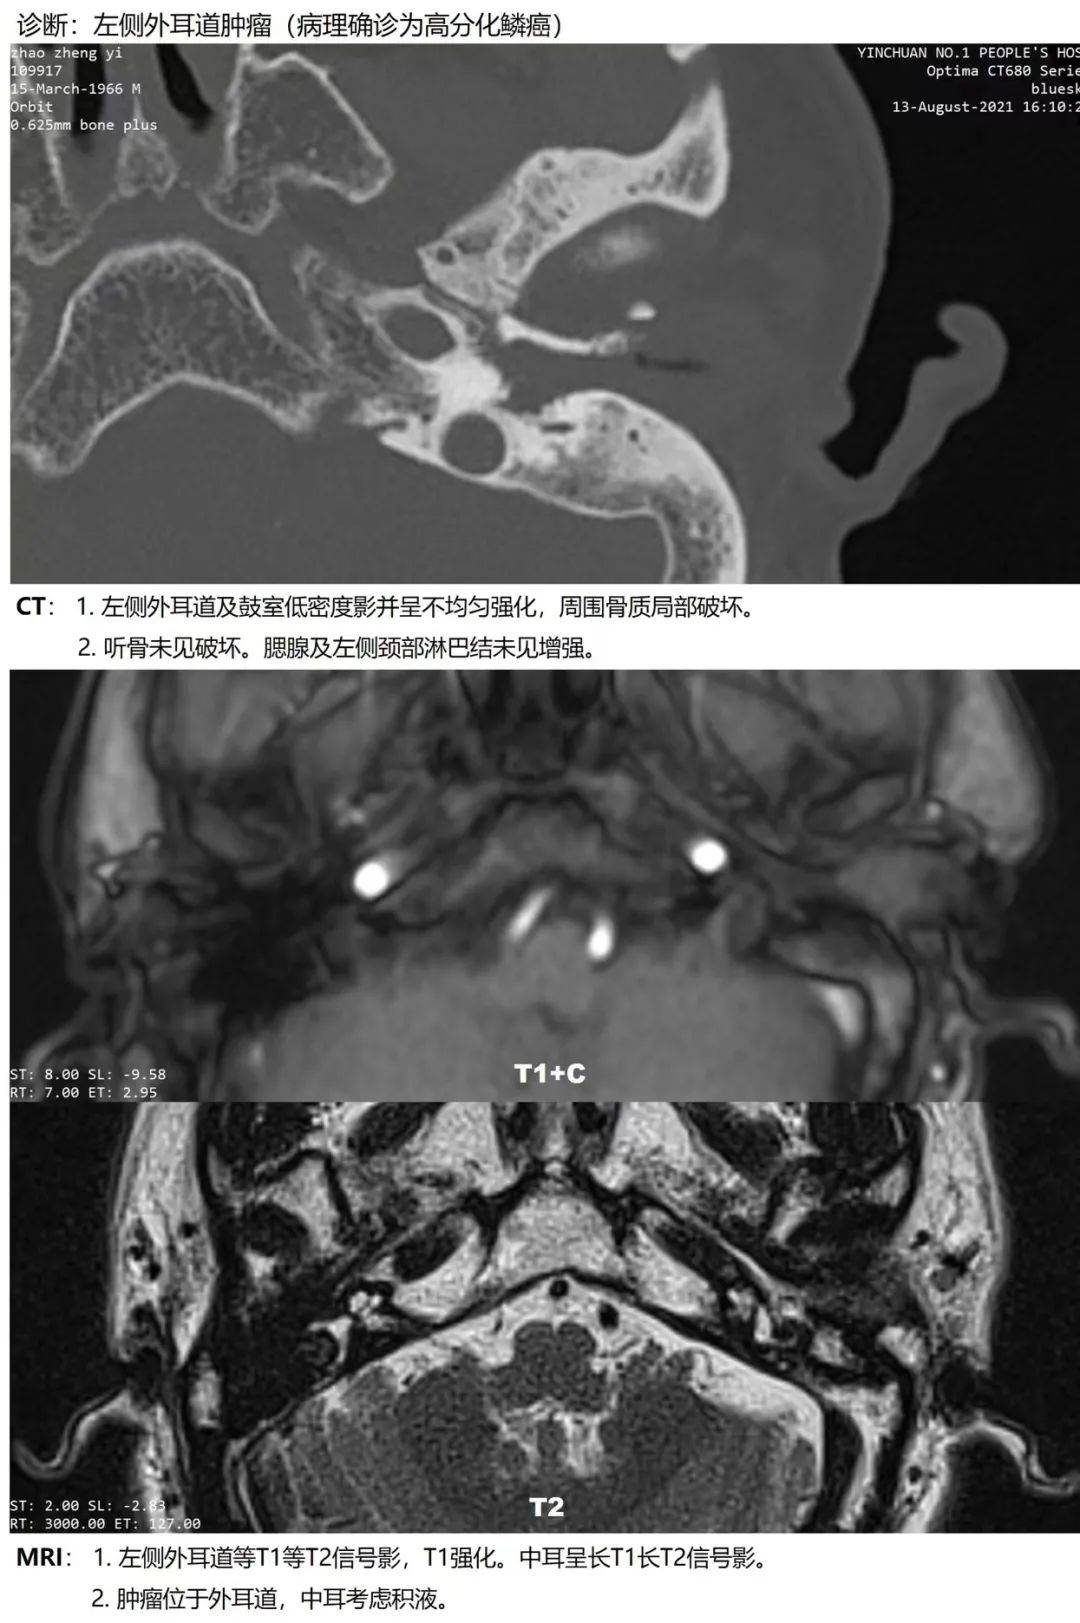

银川市一医院耳鼻咽喉头颈外科成功完成一例外耳道恶性肿瘤摘除术

图片尺寸1080x1623

外耳道肿瘤一例! - 好大夫在线

图片尺寸720x540